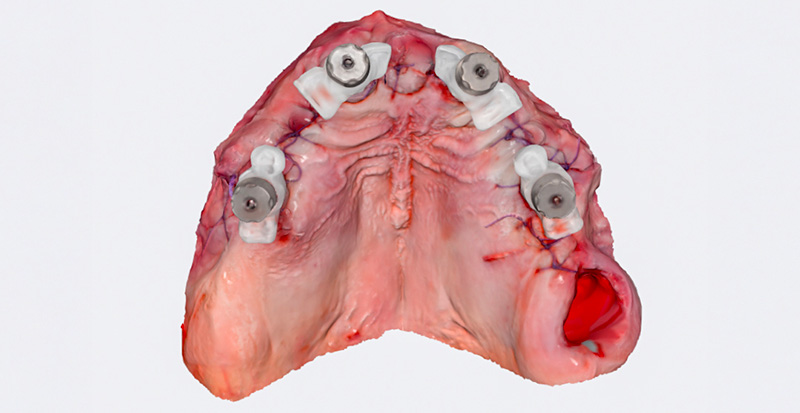

Immédiatement après la suture, des piliers de type « Scan-Transfer » de l’entreprise IPD, ont été placés sur les piliers « Multi-unit » (IPD propose des piliers « multi-unit » pour 25 marques d’implants dentaires et 80 plateformes différentes). Ceux-ci permettent une numérisation précise à l’aide d’un scanner intra-oral, selon un protocole spécifique qui évite toute distorsion de l’empreinte dans les zones édentées.

Le scan post-opératoire du maxillaire supérieur avec les « Scan-Transfers » a été réalisé dans un dossier séparé, indépendamment du scan préopératoire, et les deux ont ensuite été superposés au laboratoire. Le scan a été effectué avec un scanner intra-oral Medit i700, et le matching des empreintes a été réalisé dans le logiciel Exocad en se basant sur les zones fixes du palais et des tubercules du maxillaire.

Dans des cas plus complexes, des repères temporaires additionnels peuvent être ajoutés pour faciliter le matching. Les Scan-Transfers présentent la particularité que le matching s’effectue uniquement sur la partie supérieure de la tête du pilier d’empreinte numérique. La partie inférieure, quant à elle, peut recevoir des éléments destinés à combler les espaces édentés, ce qui facilite le scannage et réduit les risques de distorsion. La vis de fixation du Scan-Transfer, une fois vissée, est exactement au même niveau que le pilier prothétique, elle affleure la tête du pilier de numérisation. C’est un indicateur que le pilier est correctement positionné et qu’aucune déviation n’a eu lieu en raison de la présence d’un obstacle anatomique.

Fig. 05 : Scan-Transfers IPD en place.